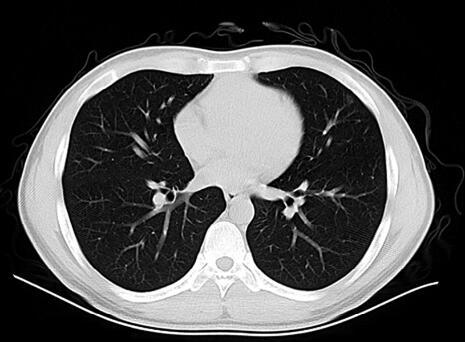

经莫西沙星5天治疗,胸部CT(复查):左肺上叶磨玻璃影较前吸收(图2)。体温稍降低,但仍可达38.0℃(图3)。

图2